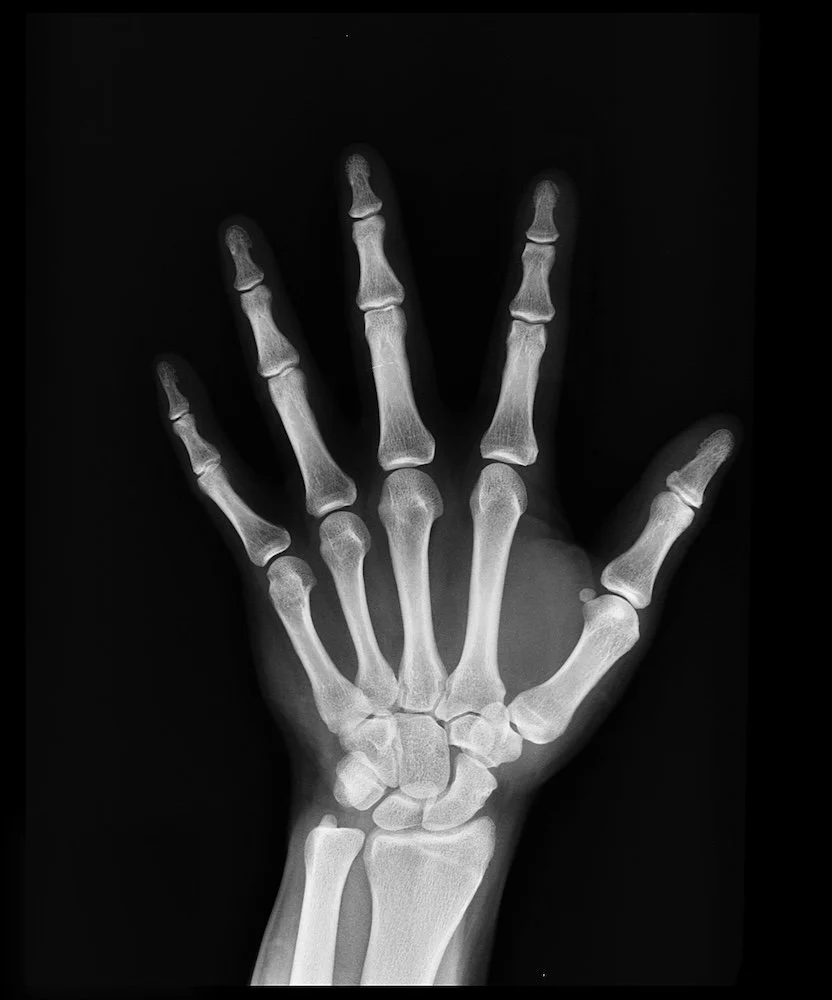

The Crisis: What Menopause Does to Your Bones

Oestrogen protects your bones. It slows down the cells that break down bone and supports the cells that build new bone. When oestrogen drops during menopause, that protection vanishes.

In the first 5-7 years after menopause, women can lose up to 20% of their bone density. Twenty percent. Gone.

After that initial rapid loss, you continue losing about 1-2% per year.

By age 50, one in two women will experience an osteoporosis-related fracture in their lifetime.

Hip fractures have a 20% mortality rate within the first year. Not from the fracture itself, but from the complications—immobility, pneumonia, blood clots, loss of independence that follows.

Women lose bone density six times faster than men after menopause.

There are no symptoms. No warning signs. No pain. Until something breaks.